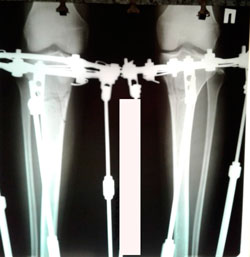

Дата операции - 21.08.2020

на фиксации

дата снятия аппаратов - 04.11.2020